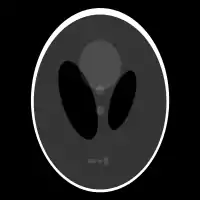

| Fantasma de Shepp-Logan; Transformada de Radon; y Transformada de Radon inversa | ||

Existe un algoritmo inverso de la transformada de Radon computacionalmente eficiente para el caso bidimensional llamado retroproyección filtrada. Primeramente consideremos el operador adjunto de :

lo que significa que la imagen original puede ser recuperada del 'sinograma' aplicando un filtro rampa (sobre la variable ) y entonces retroproyectando. Como que el paso de filtrado puede ser implementado de forma eficiente (mediante técnicas de procesamiento digital de señales) y la retroproyección no es más que una acumulación de valores en los píxeles de la imagen, resulta un algoritmo altamente eficiente, por lo que se trata de un algoritmo ampliamente usado.